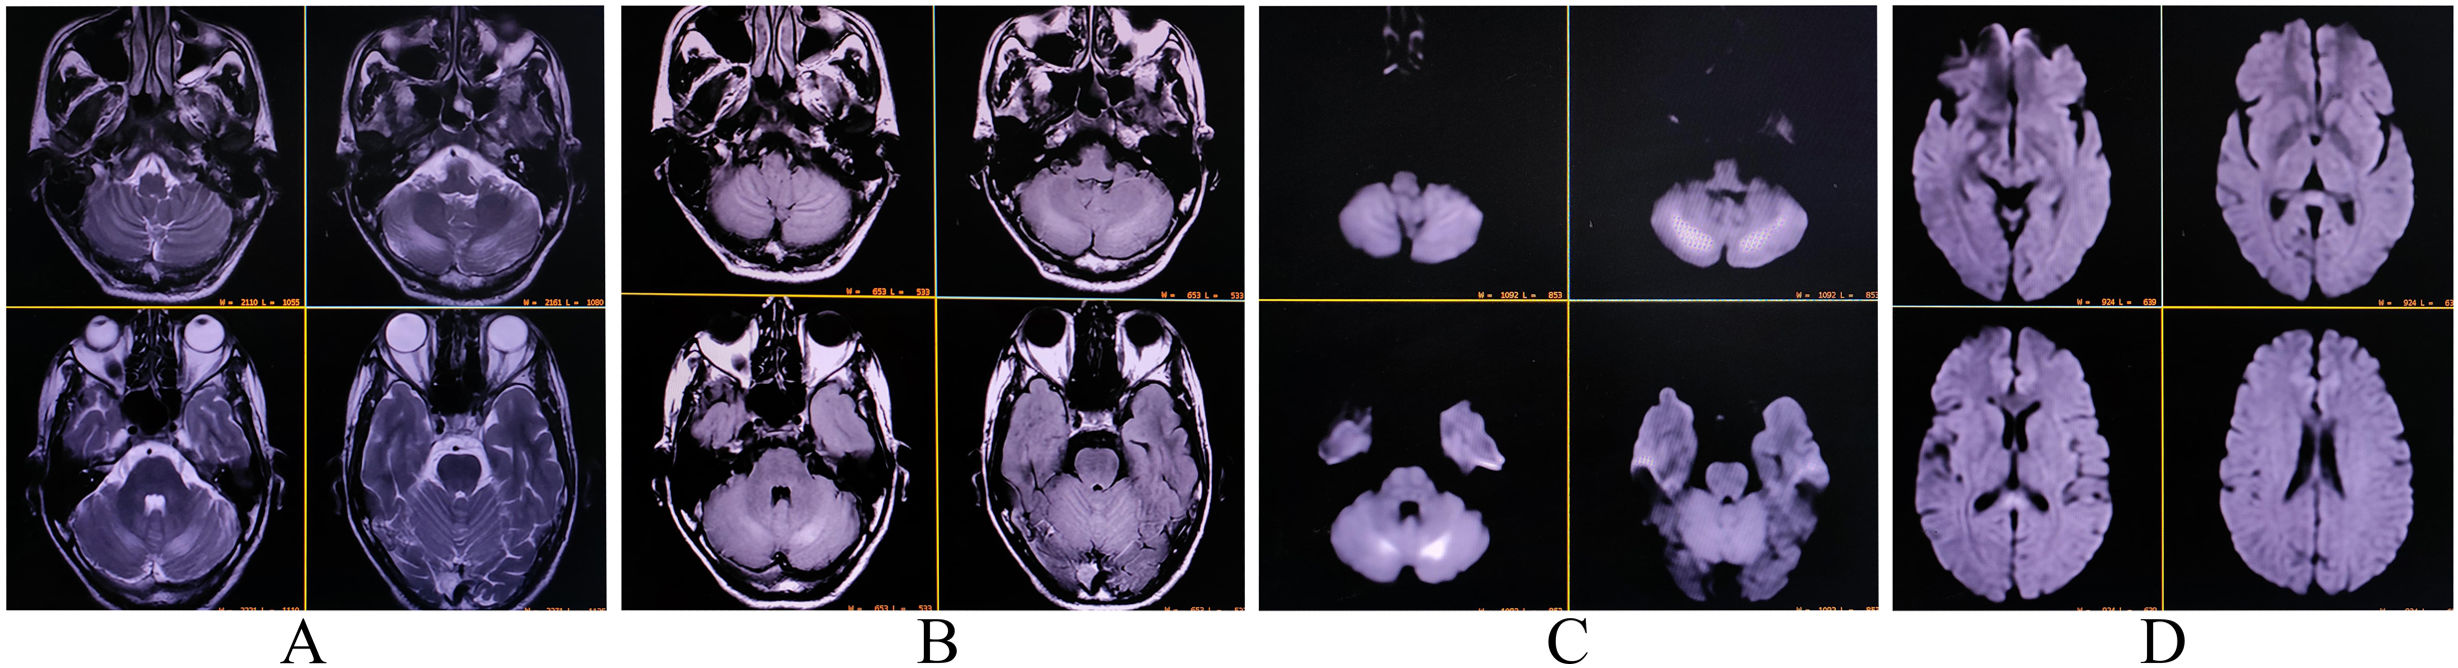

Signo de la banda motora en el PET/TC 18F-FDG cerebral: ¿un biomarcador de enfermedad degenerativa de primera motoneurona? A propósito de 3 casos y revisión de la literatura

Introducción Las enfermedades de motoneurona (EMN) incluyen afecciones como la esclerosis lateral amiotrófica (ELA) y la esclerosis lateral primaria (ELP), caracterizadas por la degeneración progresiva de la primera y/o segunda motoneurona. La identificación de biomarcadores […]